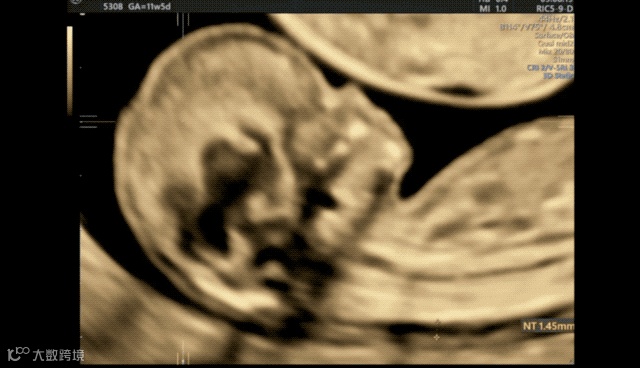

接着继续放大a平面,使胎儿头胸部占据整个画面,微调后显示NT的两条线,降低增益,完成NT测量就可以了。